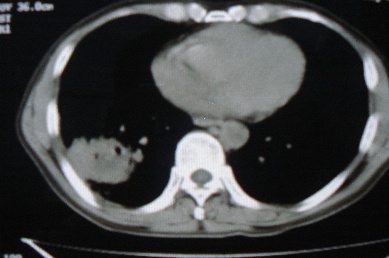

ct10716,男,59岁。发热咳嗽一天,咯血一次入院。

病灶中心有低密度,气体,病灶周围炎性浸润可能为肺脓肿,量体温、查个痰就是了,但肺脓肿一般都多少会有点兄水的。左肺下局部密度减低,小叶中心肺气肿。

病灶边缘较模糊,中心见低密度影及少量气影,宽基与胸膜相连,周围见炎性浸润,考虑右下肺脓肿。

病灶边缘较模糊,中心见低密度影及少量气影,宽基与胸膜相连,周围见炎性浸润,考虑右下肺脓肿。建议治疗后复查。

右下肺病灶,边缘模糊,中心见低密度坏死区及气体影,结合病史较短,以发热为主,考虑右下肺脓肿,建议抗炎治疗后复查。